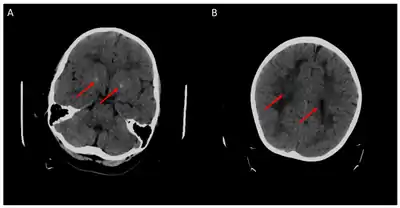

a)Extensive white matter disease b) atrophy of frontal hemispheres and cerebellum

Cerebral CT-scan at 4 years old. Red arrows show brain calcifications (A) and diffuse white matter abnormalities (B). From Mafi et al., 2020[15]